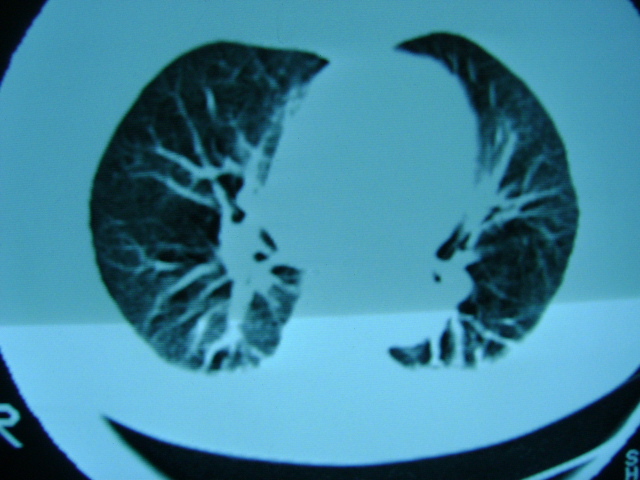

朋友的母亲,56y,咳嗽三个月,感觉左肺门不对,请大家给点意见

肺内应该存在感染

慢支 !不放心可追踪复查。

左肺门未见异常‘右肺有少许感染,图象质量不好